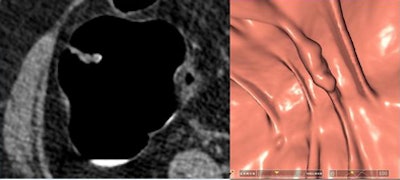

Two lesions were detected only by CAD and were not reported by the radiologists as flat due to low conspicuity. Two lesions with heights < 1 mm weren't seen at CTC but were detected at conventional colonoscopy.

| Two lesions with heights < 1 mm weren't seen at CTC despite optimal technology. Above, "carpet" lesion not visualized at CTC. |